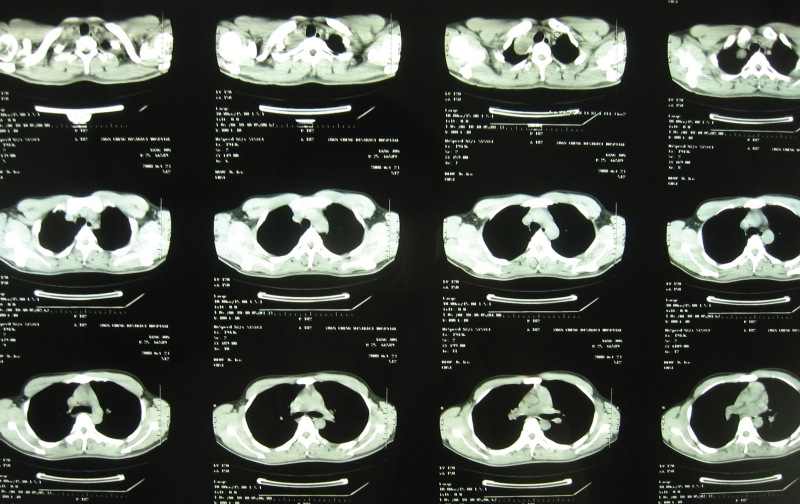

标题: CT16295:男22岁,招工体检发现。自诉右肩不适。 [打印本页]

标题: CT16295:男22岁,招工体检发现。自诉右肩不适。

图像太小了,看不清,考虑气管囊肿可能

根据部位及边缘情况考虑支气管囊肿,可惜图像太小

右上肺尖囊性病变,气管囊肿或肺囊肿都有可能。

图像确实太小,不利于诊断。但纵隔神经源性肿瘤应该没问题。考虑鞘瘤。

支气管囊肿或胸内甲状腺肿,前者可能性大吧